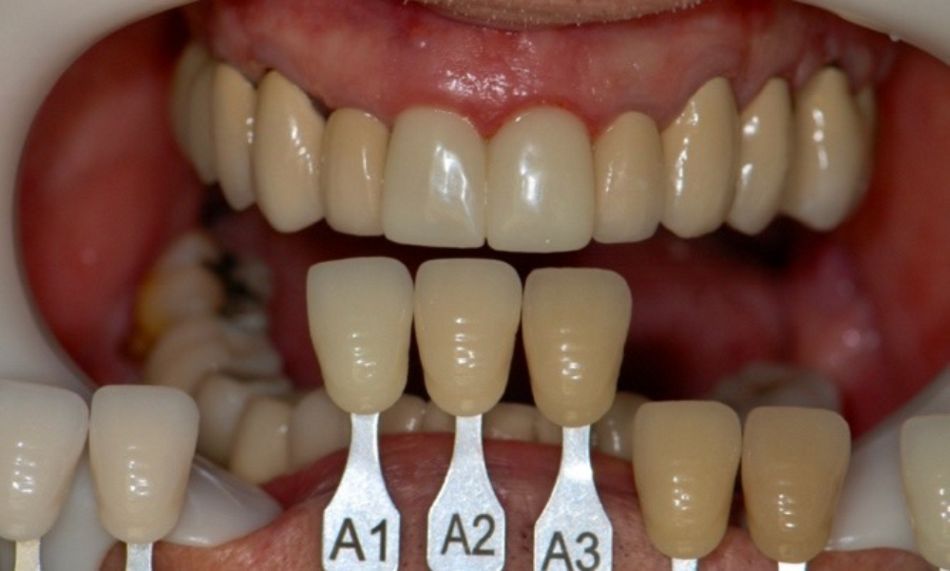

Three months later, scan bodies were placed directly on implants, and a digital impression was taken (Figs. 31,32). The color for the final crowns was chosen with the patient (Fig. 33).